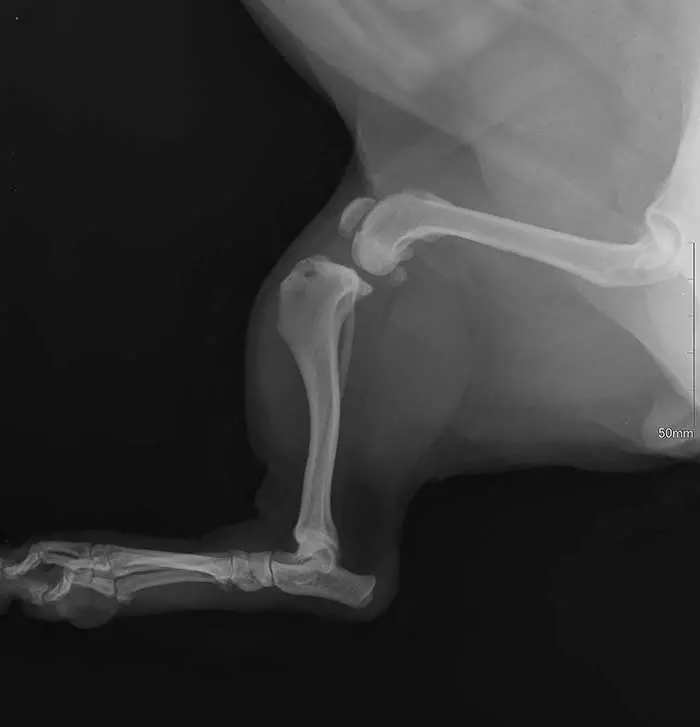

Do zerwania więzadła dochodzi najczęściej na skutek zeskoku z wysokości lub nieprawidłowego postawienia łapy (zdj. 3). Siły obciążające staw kolanowy oraz wspomniane wyżej więzadło są tak duże, że powodują jego zerwanie, szczególnie gdy więzadło to było już osłabione wskutek np. wieku bądź patologicznej budowy w obrębie stawu. Objawia się to natychmiastową kulawizną oraz charakterystycznym utrzymywaniem stawu kolanowego w postaci zgiętej. Za pomocą testu szufladowego lekarz weterynarii może potwierdzić diagnozę, jednakże podstawą jest wykonanie badania RTG. Jedynym sposobem leczenia urazu jest zabieg chirurgiczny. Najczęściej wykonuje się zabieg TPLO lub TTA, a także stabilizację zewnątrztorebkową.

Zdj. 3. Pacjent z uszkodzonym więzadłem krzyżowym przednim